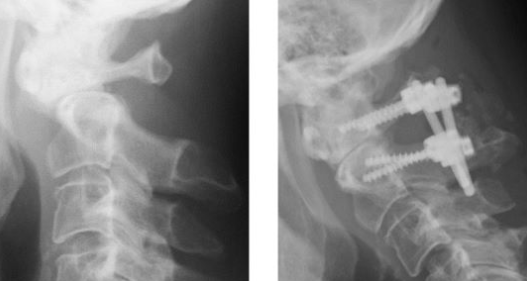

後方より椎間板の間に補強材(ケージと呼ばれています)を入れて、医療用のネジ(スクリュー)で固定して、安定させる方法です。